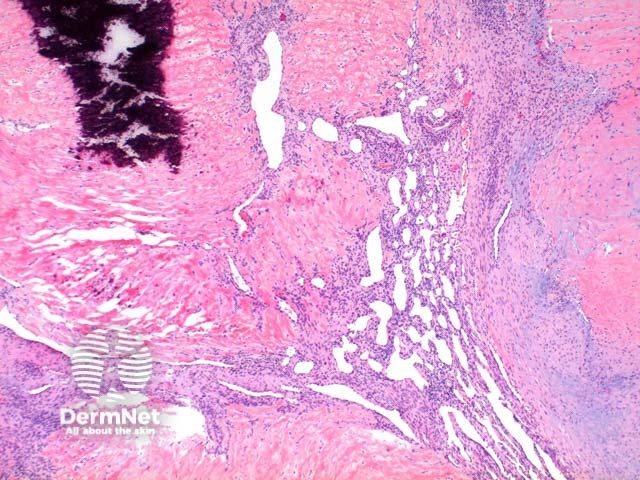

Low power view of myofibroma demonstrates a well defined multinodular tumour arising in the deep dermis or subcutis (Figure 1). Also at low power a branching ‘staghorn’ like pattern of blood vessels can be seen between the tumour nodules (Figure 2). Areas of calcification can often be seen (Figures 2, 3 and 5). The tumour nodules are comprised of a spindle cell proliferation with short plump nuclei (Figures 4,5 and 6). A basophilic tinge in the spindled peripheral component of the nodules is evident (Figures 7 and 8). Sclerotic collagen in the centre of the tumour nodules gives a biphasic appearance to the tumour (Figure 9).